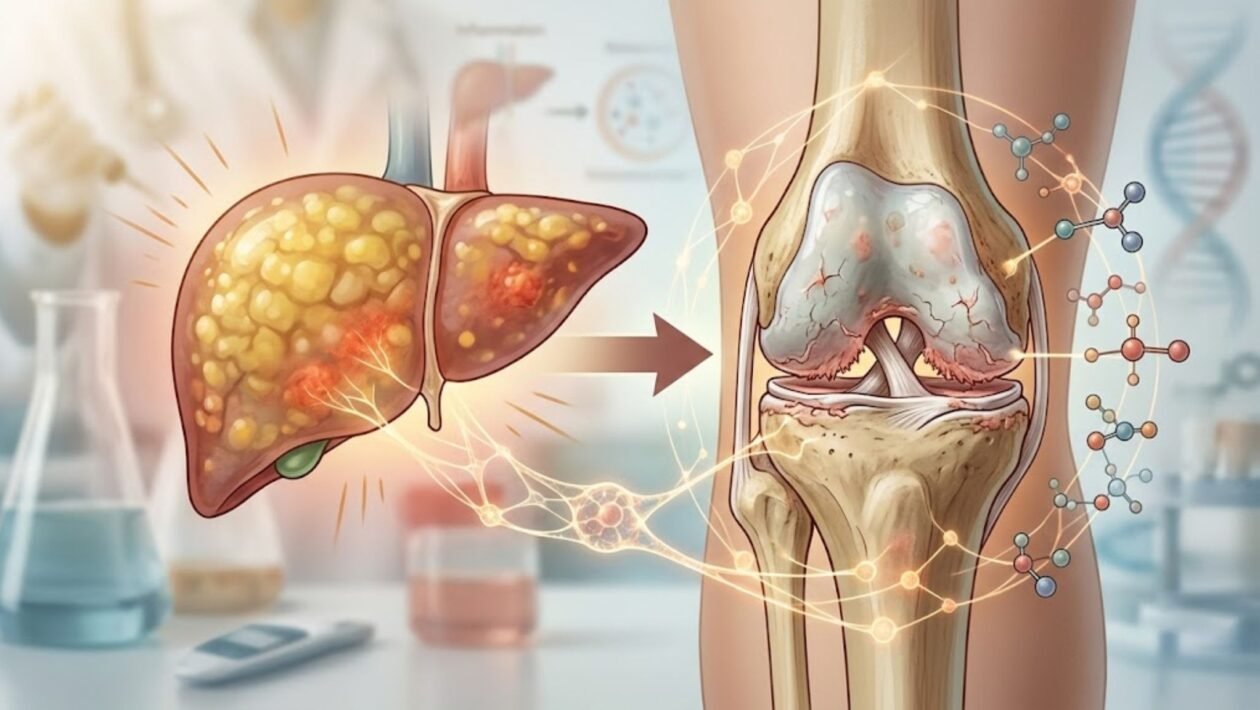

A relação entre diferentes sistemas do corpo humano pode ser mais profunda do que se imaginava. Um novo estudo de grande escala levanta uma associação importante entre doenças hepáticas metabólicas e o risco de desenvolvimento de osteoartrite, uma das condições articulares mais comuns e incapacitantes no mundo.

As condições conhecidas como doença hepática gordurosa associada à disfunção metabólica (DHGMA) e doença hepática esteatótica associada à disfunção metabólica (DHEMAM) estão diretamente ligadas ao acúmulo de gordura no fígado e alterações metabólicas importantes.

Além disso, essas condições não afetam apenas o fígado. Elas parecem estar associadas a processos inflamatórios e metabólicos que impactam outras regiões do corpo.

A conexão inesperada com a osteoartrite

Um dos principais achados foi o aumento significativo do risco de osteoartrite em pessoas com doença hepática metabólica.

A ligação entre metabolismo, fígado e saúde das articulações

De forma geral, os achados indicam que o corpo funciona como um sistema interligado. Assim, alterações metabólicas no fígado podem refletir em outros tecidos, como as articulações.